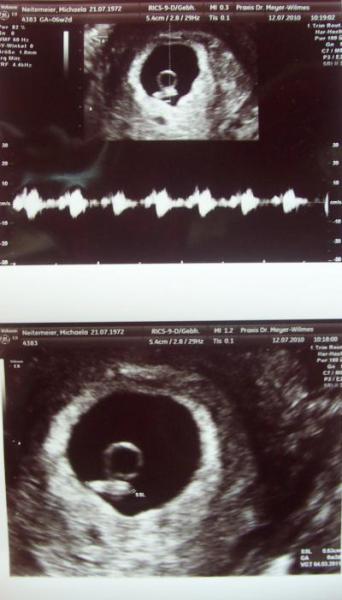

Huhu Heute morgen hatte ich endlich meinen FÄ termin - war ganz schön aufgeregt - aber mein Lebensgefährte hat mir die aufregung ein wenig genommen - puhhhh .... tat gut das er bei mir war nun - mit unserem Krümelchen ist alles ok - der US war super schön - ist jetzt 6.3mm / Termingerecht.- Herzchen bubbert - wir haben es gesehen und gehört - einfach nur schön - In 14 Tagen muss ich erneut zu ihr zwecks Blutbild etc.pp - schaut auch nochmals auf´s Krümelchen . na und dann heisst es - alle 4 wochen wieder. Lg Michaela

Bild zu Hatte heute meinen FÄ Termin - freu - - Forum für März - Mamis